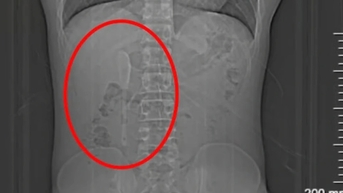

복강경 수술

희귀질환의 성공적인 진단 및 수술